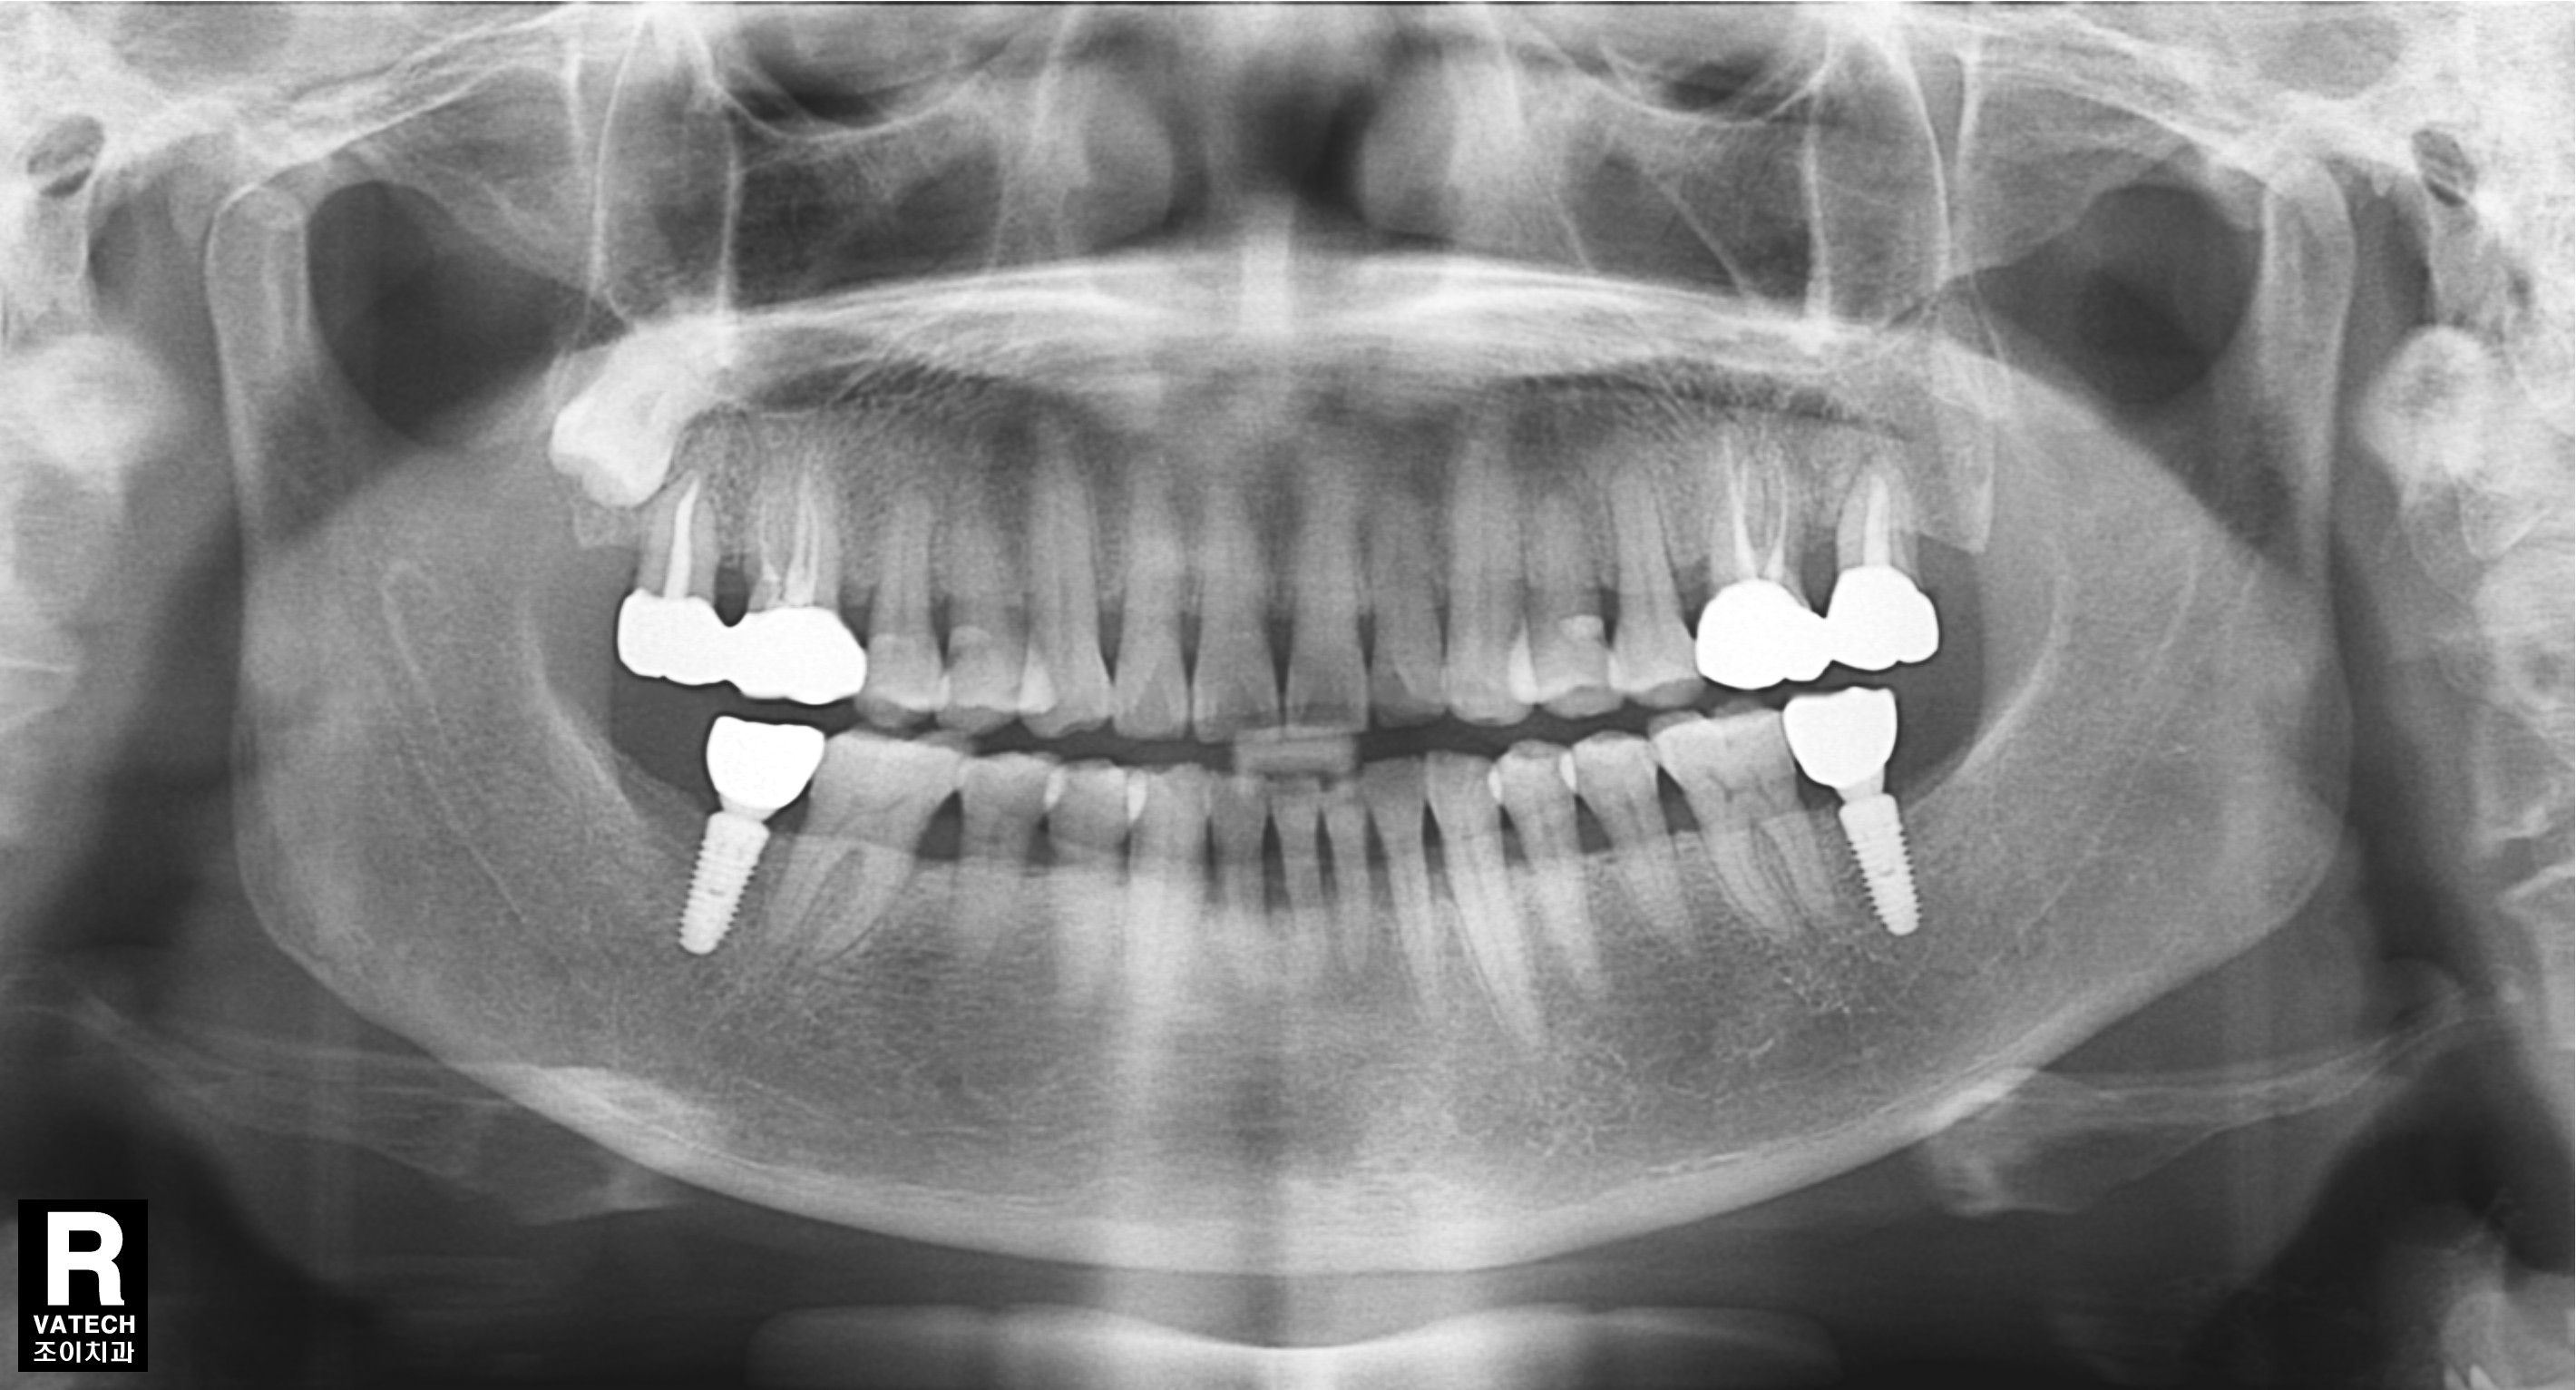

[임플란트] 제목 : 하악구치부 임플란트

이가 빠지면 반대편 이가 정출되어 공간이 좁아지게 됩니다.

이런 경우에 반대편 이도 치료를 하여 공간을 만들어 준 후 임플란트를 식립하여야 합니다.